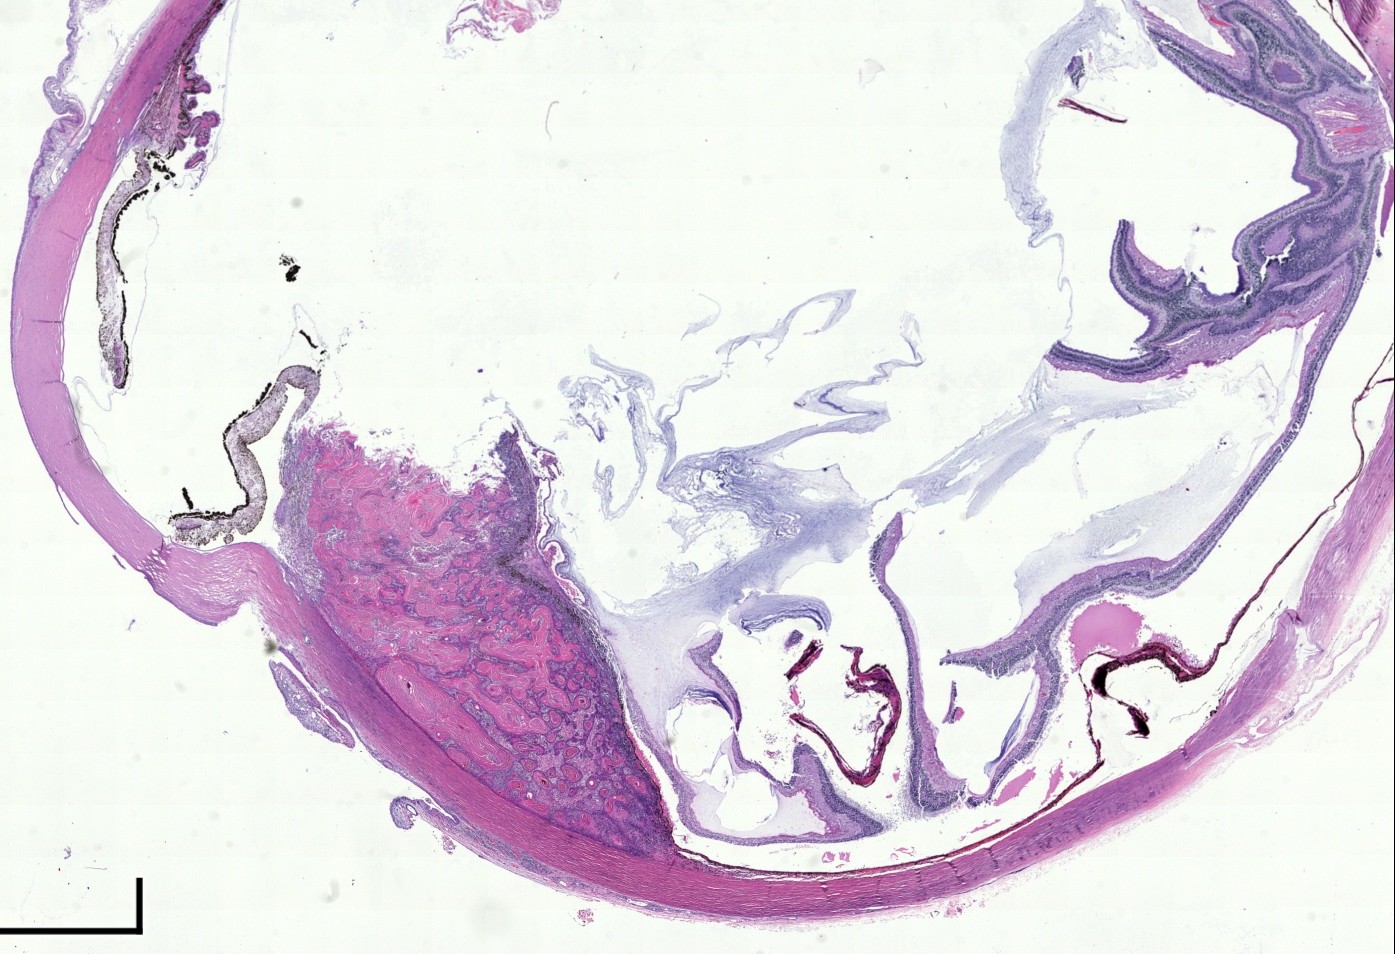

El diagnóstico sobre muestras de tejidos y líquidos corporales en plena era de la medicina del futuro, está basado en la integración de técnicas y conocimientos diferentes.

Hoy más que nunca es importante integrar una buena historia clínica con un correcto estudio de imagen y una buena morfología que además puede estar apoyada con proceso especiales complementarios relacionados con la Inmunología, Biología Molecular y Citogenética, generando así un estudio integral conocido como Patología Molecular.